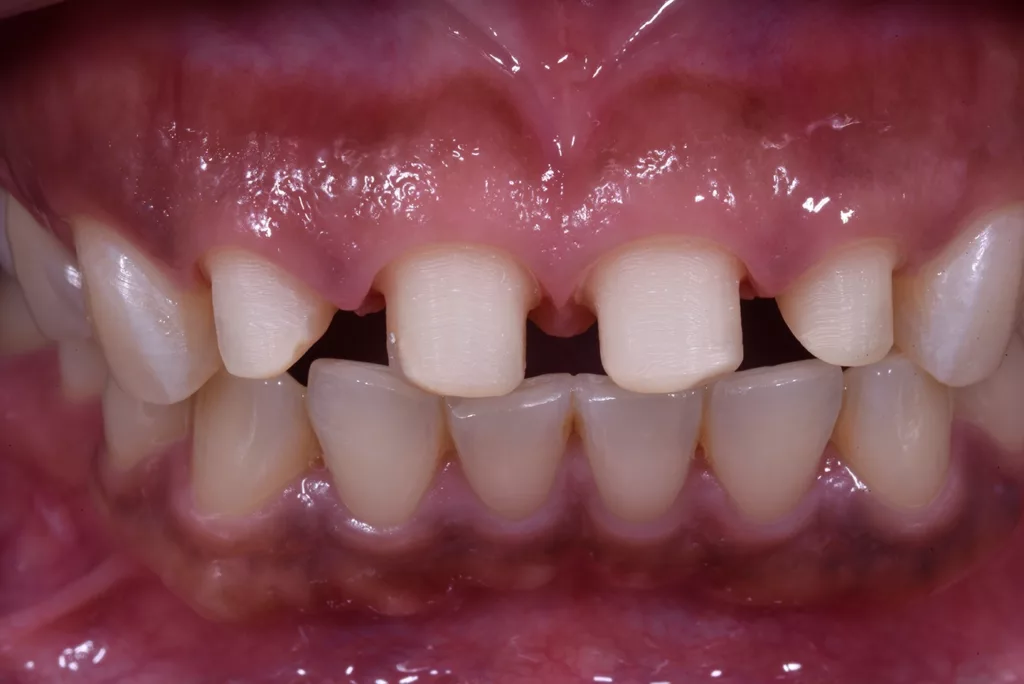

Um die Zähne 21 und 22 so vital wie möglich zu erhalten, wurden sie rundum lediglich um ca. 1,5 mm reduziert. Bei den Zähnen 11 und 12 war dies vor allem inzisal nicht möglich, da sie nach der Entfernung des Metallstiftes und des Kunststoffes stark reduziert waren, jedoch nicht so stark, dass eine Wurzelbehandlung notwendig gewesen wäre. Die Zähne wurden anschließend mit neuen Kunststoffaufbauten versorgt und für monolithische Zirkoniumdioxidkronen präpariert. Während der provisorischen Versorgung wurden die Zähne regelmäßig kontrolliert, um den Erfolg der Restauration und das Ausbleiben von Komplikationen sicherzustellen (Abb. 53 bis 56).

Die Kronen wurden in diesem Fall aus dem Material IPS e.max® ZirCAD Prime Esthetic von Ivoclar angefertigt. Die Transparenz des gewählten Zirkoniumdioxids ermöglichte die Fertigung dünner Kronen von 0,5 mm und gleichzeitig eine präzise Farbreproduktion ohne dicke Schichtung. Das Stumpfdesign wurde so gewählt, dass das Zirkoniumdioxid bis zur Inzisalkante reichte, um Schneidekantenfrakturen zu vermeiden. Die Schichtung erfolgte durch Auftragen von IPS e.max® Ceram Dentin-Pulver (OE1, OE2 und T1) auf das Grundgerüst (Abb. 57 bis 63).

Die fertigen Kronen nahmen die natürliche Zahnfarbe auf und überzeugten durch eine außergewöhnliche Transparenz. Obwohl die Präparationsrichtlinien für Frontzähne eine Kronendicke von 0,8 mm vorsehen, erfolgte aufgrund der Vitalität der Zähne eine möglichst geringe Präparation. Zwar erschienen die beiden mittleren Schneidezähne zunächst etwas kürzer, aber tatsächlich wurde die Länge der Kronen unter Berücksichtigung der aufgezeichneten Frontzahnführung der Patientin angemessen bestimmt. Durch diese Vorgehensweise lässt sich sicherstellen, dass die Kronen langlebig und geschützt sind (Abb. 64 bis 67).